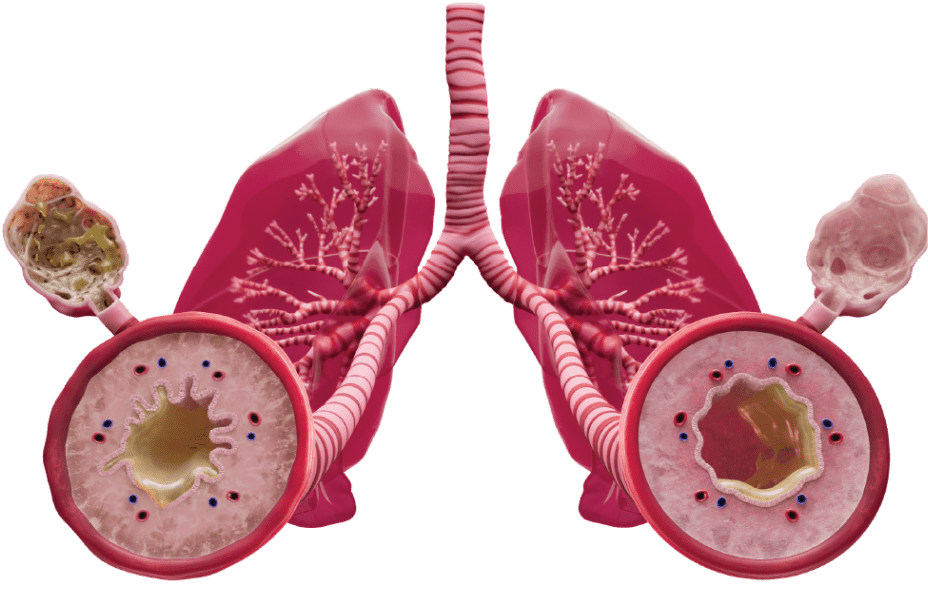

Up to 40% of COPD patients present with type 2 inflammation1-5,a

Approximately 40% of COPD patients present with elevated eosinophils, a biomarker of type 2 inflammation.1-5 Only DUPIXENT directly inhibits IL-4 and IL-13 signaling, two of the key drivers of type 2 inflammation in COPD.12

DUPIXENT is indicated as an add-on maintenance treatment in adult patients with inadequately controlled COPD and an eosinophilic phenotype.

Limitations of Use: DUPIXENT is not indicated for the relief of acute bronchospasm.